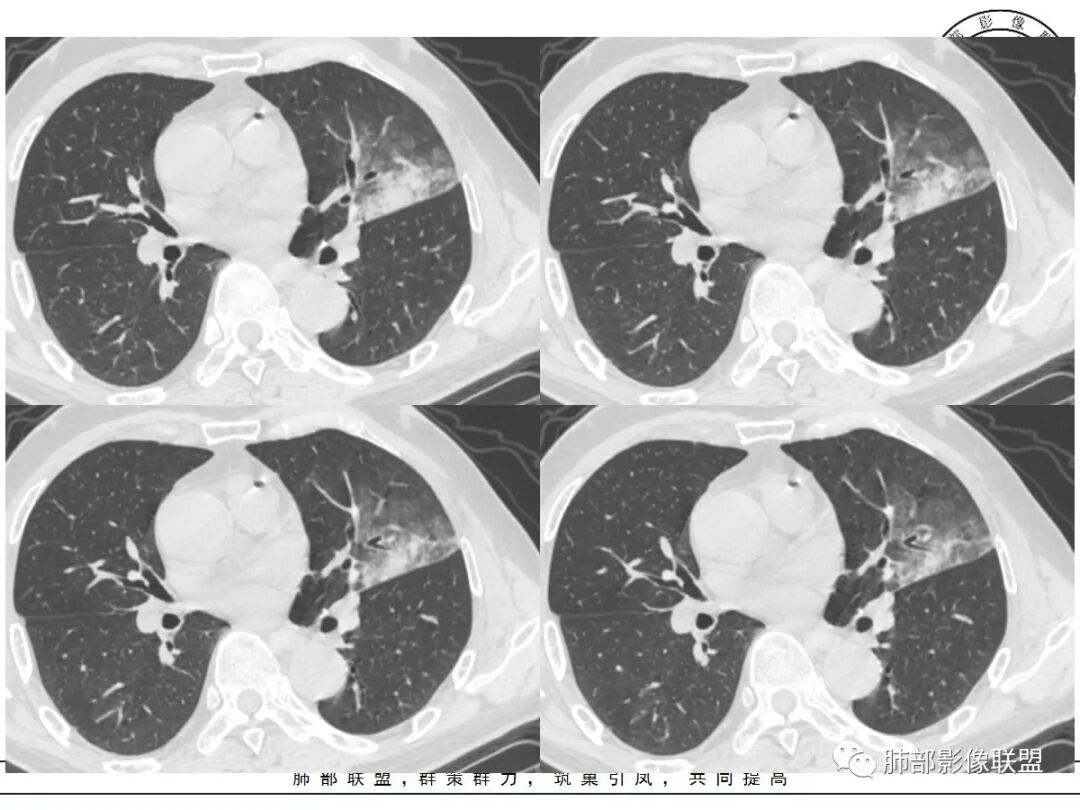

左肺上叶类圆形软组织影,边界较清楚,其内密度均匀,外侧缘可见空气新月征,并可见点状钙化,增强扫描可见均匀强化,病灶周围可见磨玻璃渗出性密度影,斜裂侧光滑平整。考虑炎性病灶,以肉芽肿性炎症为主(如真菌性肉芽肿),鉴别结核(无卫星灶,无多态性),肺癌(无毛刺,分叶等恶性征象,)细菌性炎症(密度一般不这么致密,很少钙化及空气新月征)。

左肺上叶类圆形软组织影,界清,内见空洞影,病灶周围斑片影,可见空气支气管征,未垮叶。考虑炎性病变,糖尿病四大金刚,肺克?毛霉?

老年男性,血糖升高六年,反复咳痰咳嗽3周,左肺上叶近斜裂类圆形肿块影,边缘伴磨玻璃影,边界不清。内部可见支气管走行、钙化、小空洞,叶间裂局部膨隆,增强扫描轻度强化,内部可见小的低密度区,边界尚清。考虑为炎性病变可能性大。

左肺叶裂旁实变影,宽基底与叶裂胸膜相连,边缘平直,部分略膨隆,病灶近段及上段支气管深入病灶内,部分壁略增厚,远端支气管截断,似有小空泡,壁规则,内部可见高密度钙化,周围可见模糊的GGO,血象正常,考虑结核(NTM),鉴别隐球菌,奴卡,放线菌。

老年男性,66,反复咳嗽、咳痰3月。糖尿病,血象不高。

胸部CT:左肺上叶类圆形肿块影,边界较清楚,密度较均匀,内可见小片坏死、偏心空洞、空气新月征、点状钙化,周围晕、絮状渗出、边缘模糊,支气管扩张、充气征、支气管进入病灶堵塞,叶裂牵拉明显,增强扫描中度均匀强化,纵隔可见淋巴结。考虑:炎性病灶,肉芽肿性炎症,曲霉?毛霉?鉴别:TB,淋巴瘤。

左上肺类圆形肿块影,边界较清楚,支气管通畅略扩张,周围磨玻璃影,其内密度均匀,外侧见空气新月征,且见点状钙化。叶间裂光滑稍膨隆。老年男性,糖尿病,高血压,痰培养克雷伯菌。综合考虑炎性病灶,克雷伯合并真菌感染,曲霉。结核合并真菌。鉴别肺癌合并感染。

左肺上叶类圆形软组织影,边界稍模糊,其内密度均匀,外侧缘可见空气新月征,并可见点状钙化,增强扫描渐进性强化,病灶周围可见磨玻璃影,斜裂侧光滑平整,气管未见明显闭塞,淋巴结未见肿大,糖尿病患者,首先考虑感染性变,结核并曲霉?